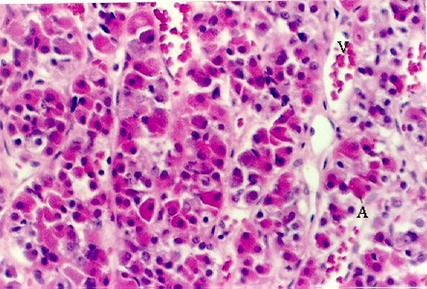

The above photos show higher magnifications of the pars distalis. You should be able to distinguish acidophils and basophils in this and your slide. To do this, look at the color of the red blood cells in the vessels (V). Then, match the color to cells in the pituitary. Those are the acidophils (A). Cells that are more "purple", or blue are the basophils (B). Cells that have hardly any color are the chromophobes. There are few true chromophobes since at the electron microscopic level most pituitary cells have the granules that are characteristic of a particular cell type. They are simply degranulated acidophils or basophils.